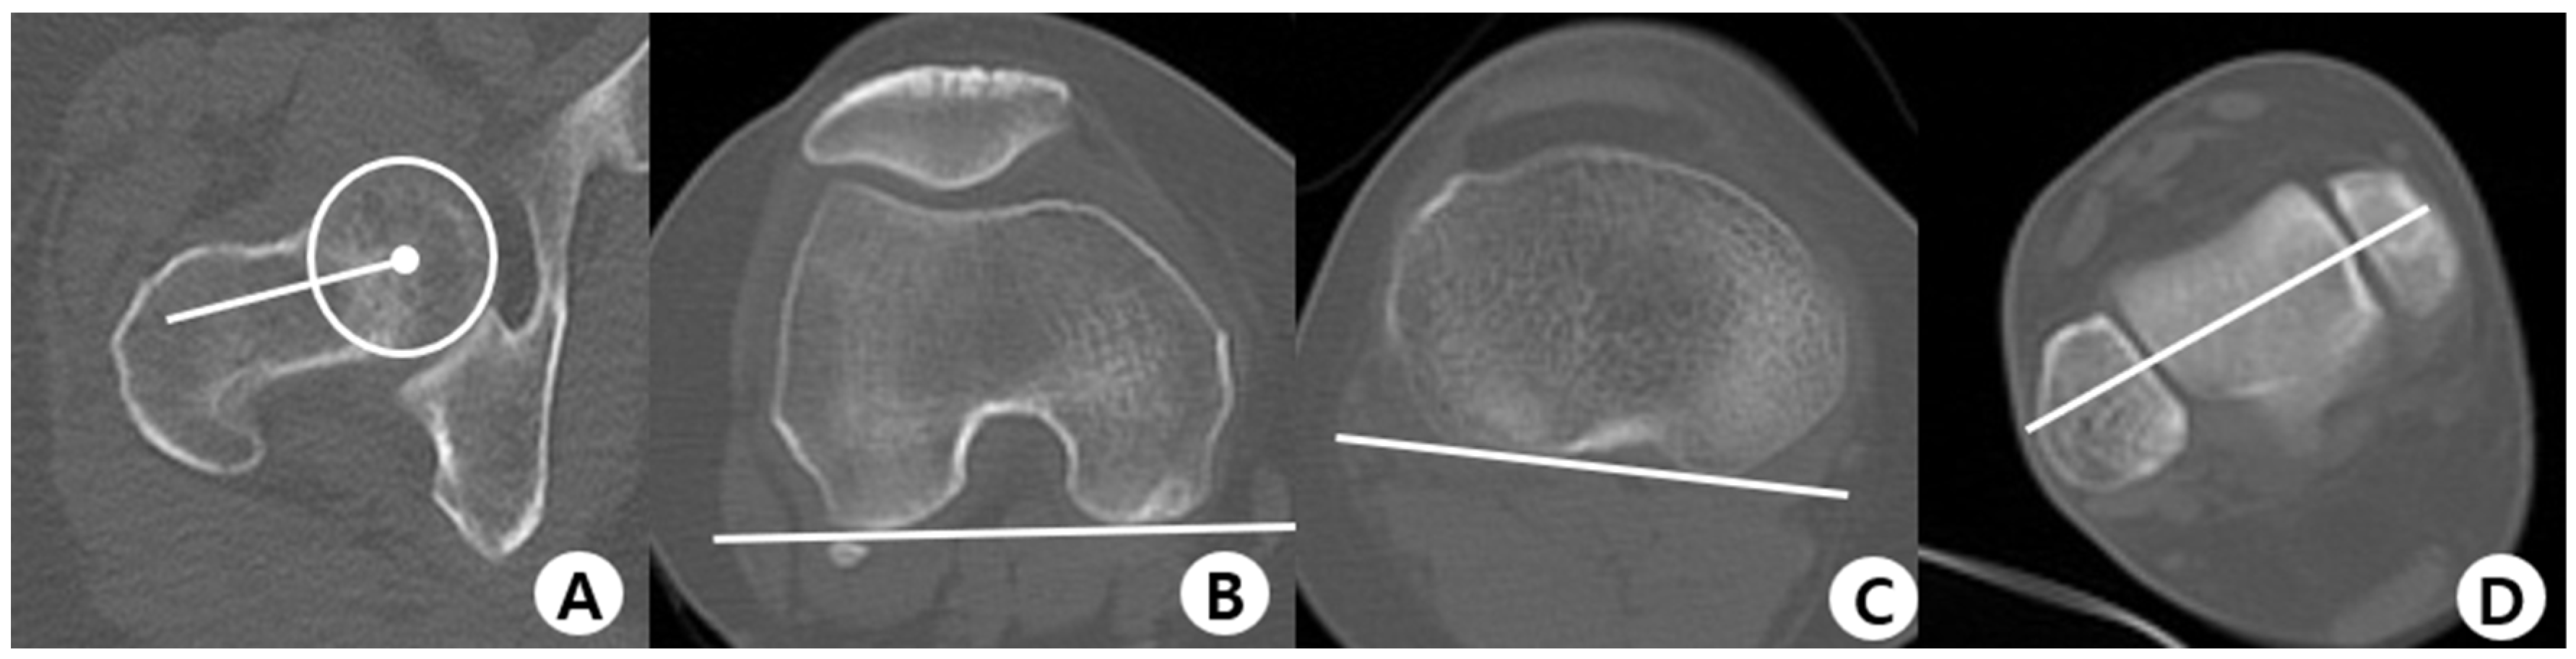

2.2. Evaluation Methods

2.3. Measurement of Parameters and Clinical Outcomes